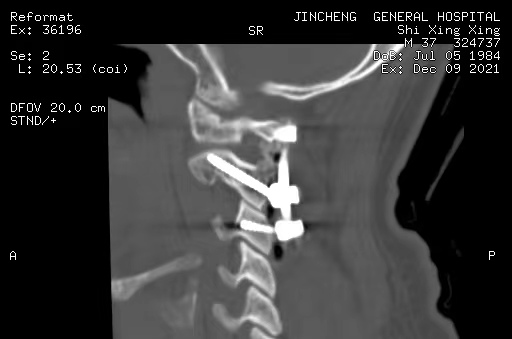

寰樞椎的內(nèi)固定治療、脊柱脊髓病損的手術(shù)治療

打破了脊柱手術(shù)生命禁區(qū)的限制,手術(shù)數(shù)量及質(zhì)量全市第一,處于省內(nèi)領(lǐng)先水平。